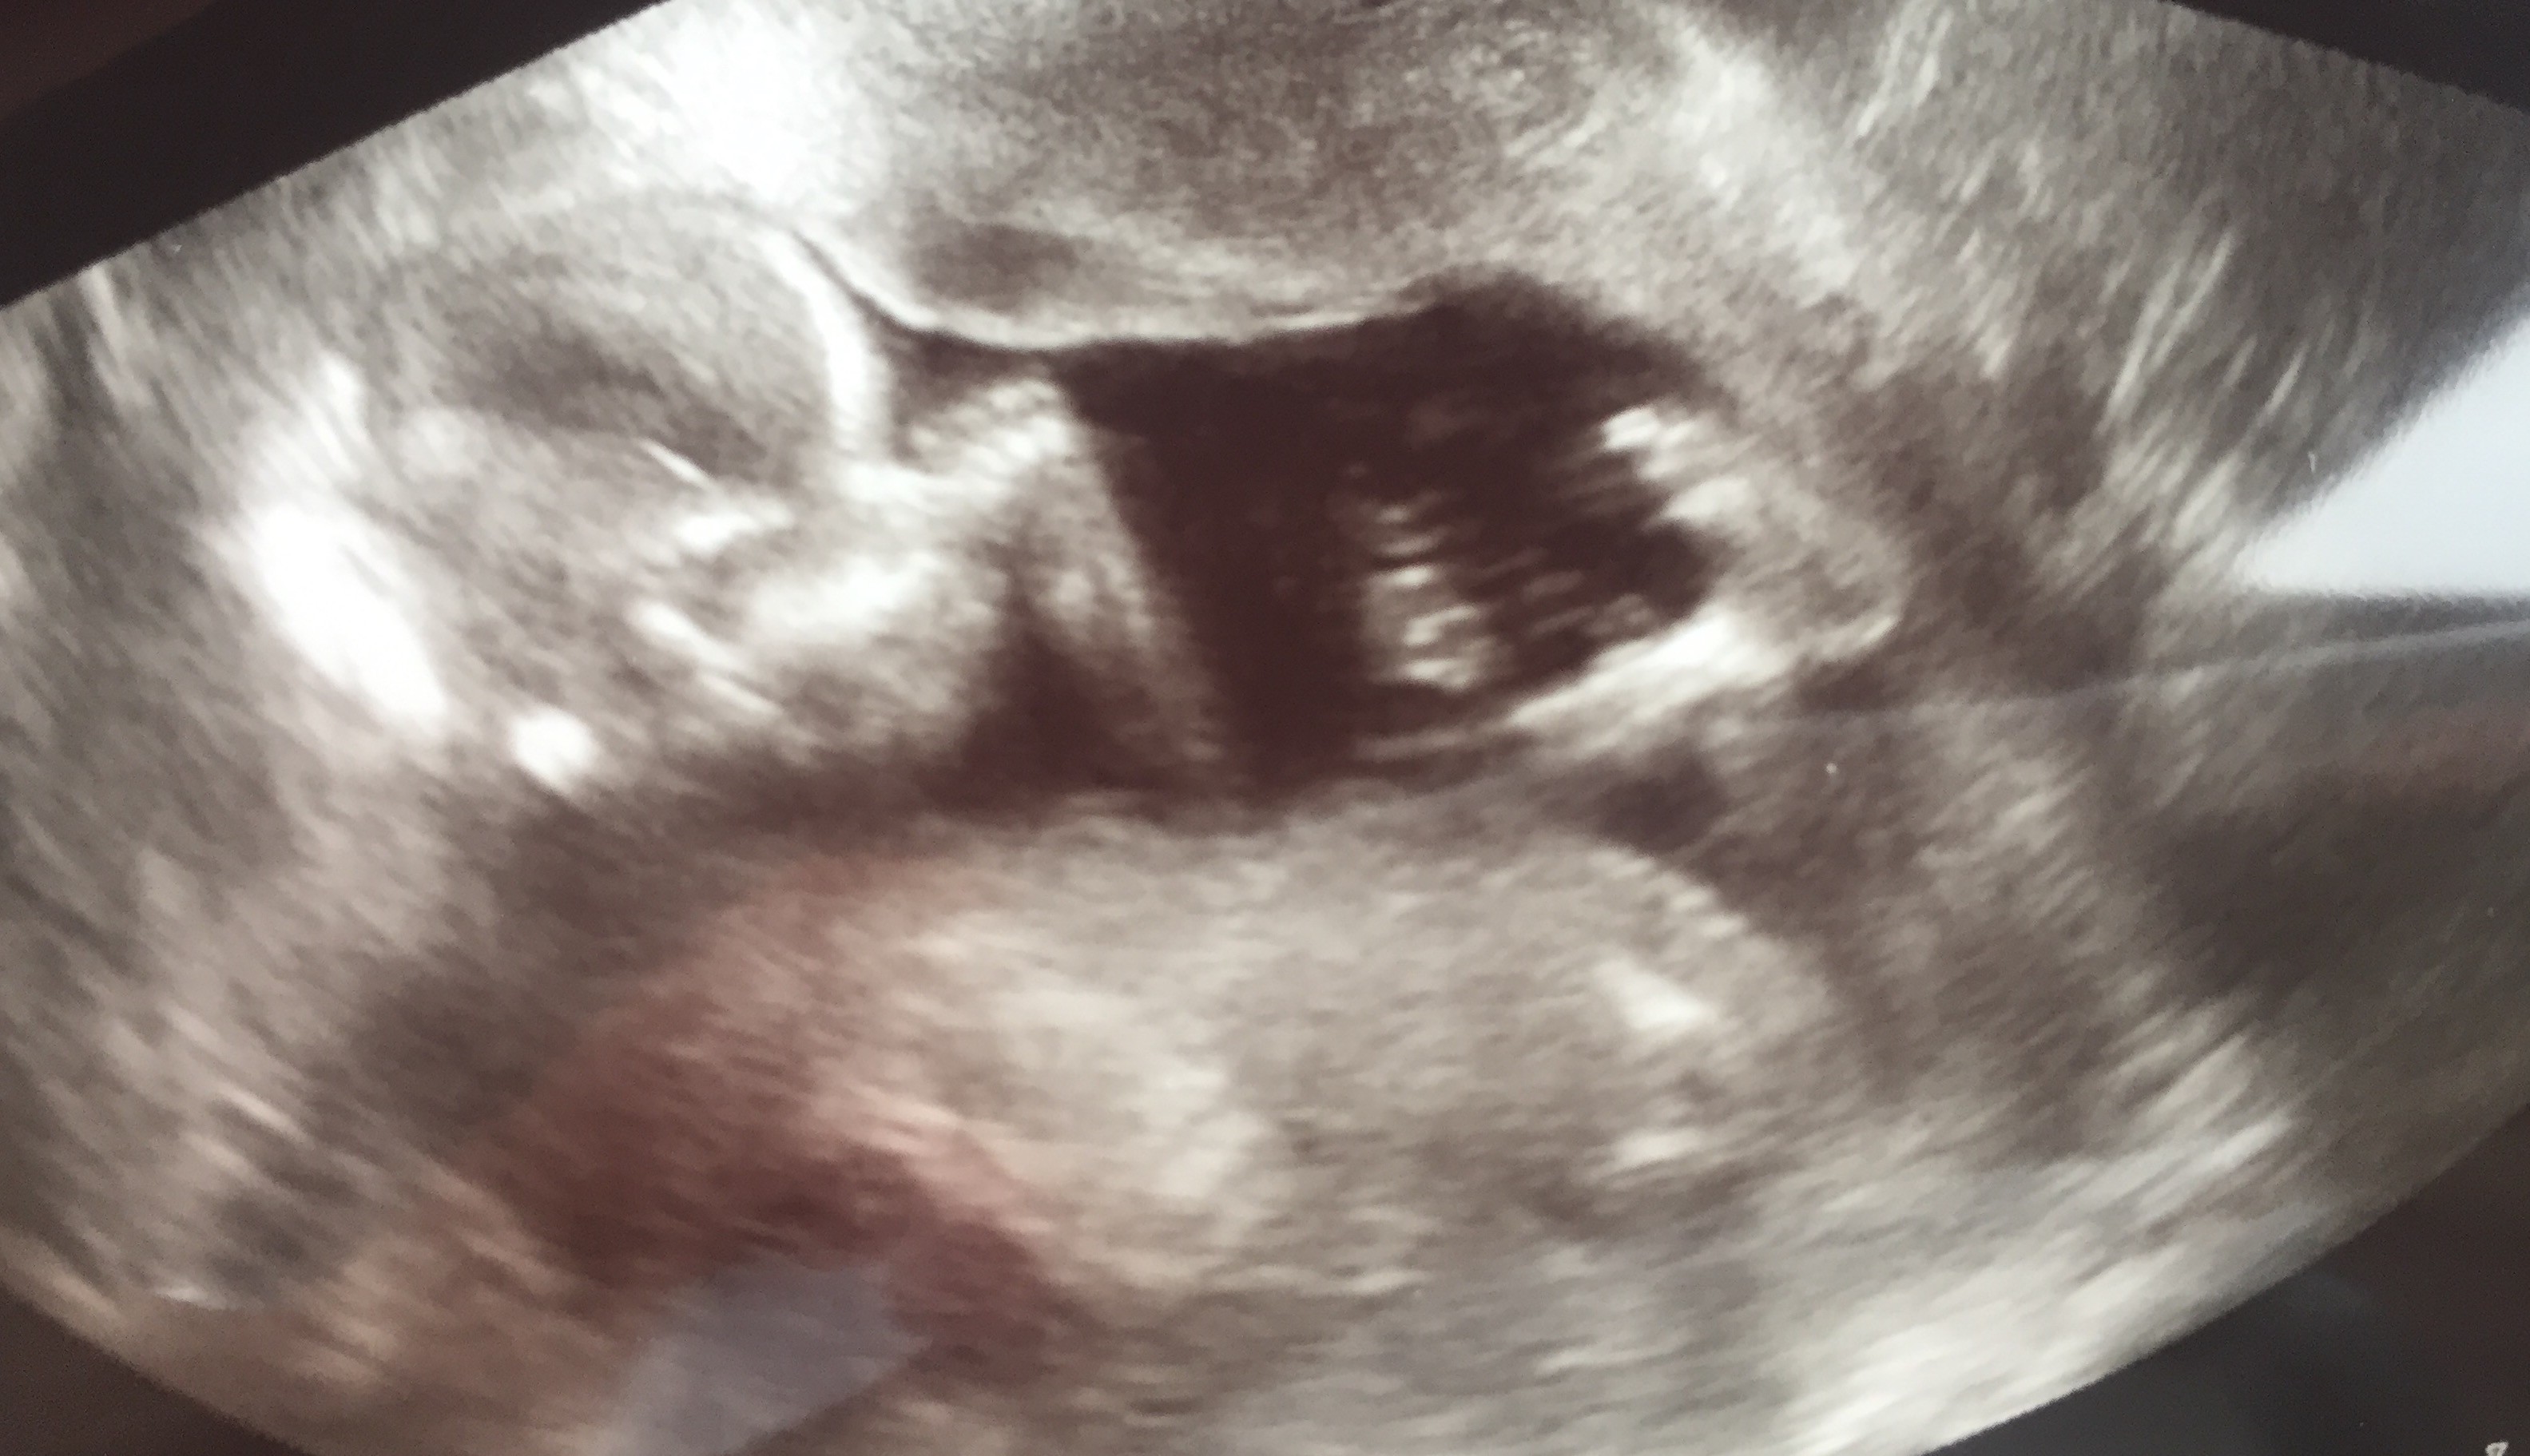

Moj synek

Ogólnie luz, noga na nogę przez całe badanie, machanie łapka i w końcu noga na nogę plus ręce za głowę

. Niesamowite jest to, że takie maleństwo już tak dobrze widać. Kocham i mam nadzieję, że bedzie dobrze do końca. Jestem po 3 stratach, ale do 9 tc.

Moj synek.

Ogólnie luz, noga na nogę przez całe badanie, machanie łapka i w końcu noga na nogę plus ręce za głowę. Niesamowite jest to, że takie maleństwo już tak dobrze widać. Kocham i mam nadzieję, że bedzie dobrze do końca. Jestem po 3 stratach, ale do 9 tc.